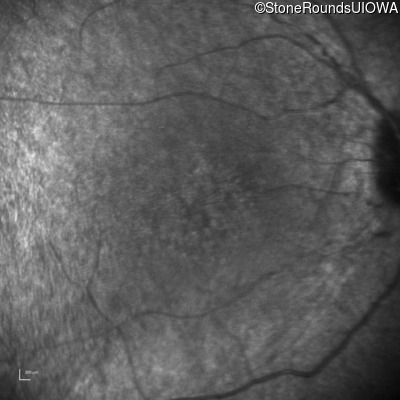

Infrared Fundus Photograph - Right - 20/200 -1

Exemplar